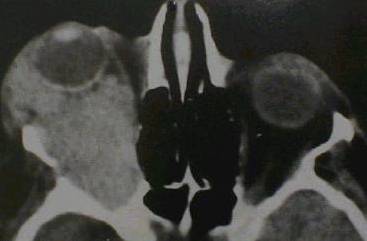

What type of image is it? CT scans or MRI scans (T1 or T2

weighted)

Which plane the image is in? axial, sagittal or coronal.

bony lesion: localized bony expansion (meningioma

and osteoma in which the lesions have the same density as the surrounding

bone; fibrous dysplasia in which the bone density is reduced)? any bony

thinning next to an orbital lesion (suggesting long-standing chronic lesion)?

any lytic lesion (suggesting malignant lesions such as metastasis or myeloma)?